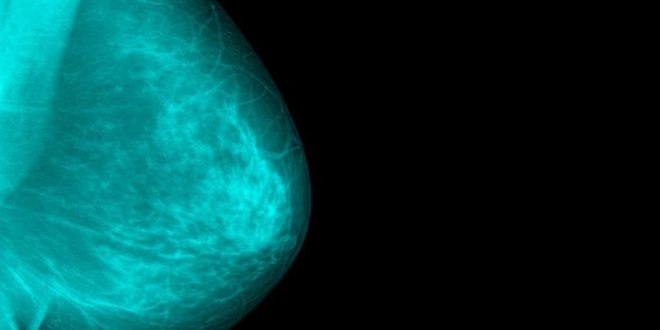

Ο κίνδυνος προσβολής από καρκίνο του μαστού μετά από μια αποβολή είναι ιδιαίτερα αυξημένος κατά τη μετεμμηνοπαυσιακή περίοδο.

Σύμφωνα με γαλλική μελέτη οι αλλαγές που επέρχονται στα κύτταρα του γυναικείου στήθους έπειτα από μια πρώτη επιτυχημένη κύηση έχει αποδειχθεί ότι παράσχουν επαρκή προστασία από τον καρκίνο του μαστού, κάτι που ισχύει όταν η πρώτη κύηση είναι αποτυχημένη.

Στο πλαίσιο της μελέτης, οι ερευνητές υπέβαλαν σε παρακολούθηση περίπου 92.000 γυναίκες, ηλικίας από 40 έως 65 ετών, σε μια προσπάθεια να συγκεντρώσουν στοιχεία σχετικά με τις συνθήκες της κύησης τους αλλά και άλλους δημογραφικούς παράγοντες.

Στη συνέχεια οι ερευνητές κατέγραψαν τον αριθμό των γυναικών που προσβλήθηκαν από καρκίνο του μαστού.

Αυτό που διαπιστώθηκε ήταν ότι από το σύνολο των γυναικών, το 22,1% είχαν υποβληθεί σε διακοπή της κύησης και το 23% είχαν αποβάλλει.

Ενώ για άγνωστους λόγους, οι γυναίκες που είχαν υποβληθεί σε δύο διακοπές κύησης διέτρεχαν κατά 25% μικρότερο κίνδυνο να προσβληθούν από καρκίνο μαστού, ο κίνδυνος ήταν αυξημένος μεταξύ των γυναικών που δεν είχαν αποκτήσει παιδιά και είχαν μία ή περισσότερες αποβολές.

Οι επιστήμονες τονίζουν ότι το φαινόμενο οφείλεται σε εξωγενείς παράγοντες, όπως την έκθεση σε χημικές ουσίες ή ακτινοβολία καθώς και σε γενετικές ανωμαλίες.

Τέλος, ο κίνδυνος προσβολής από καρκίνο του μαστού έπειτα από μια αποβολή ήταν ιδιαίτερα αυξημένος κατά τη μετεμμηνοπαυσιακή περίοδο. Αν μάλιστα ο αριθμός των αποβολών ήταν μεγαλύτερος των τριών, το ποσοστό κινδύνου άγγιζε το 50%.

Οι επιστήμονες συμπεραίνουν ότι η όποια προστατευτική δράση κατά του καρκίνου του μαστού δεν φαίνεται τελικά να αποκτάται κατά το πρώτο τρίμηνο της κύησης.